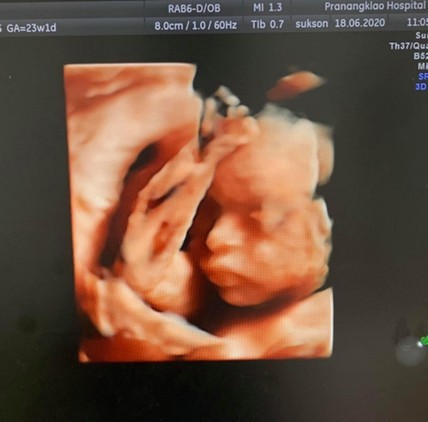

จ้ำม่ำแล้ววว😘😚

ชาวตอน28w❤